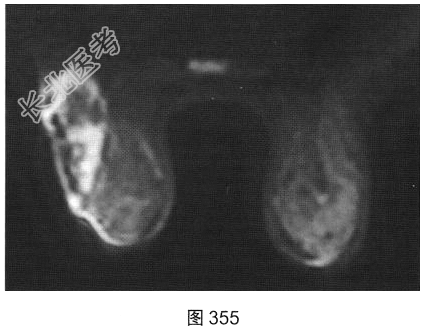

- [材料题] 患者女性,28岁,哺乳后3个月出现左乳肿胀、疼痛,患者无发热。既往体健。查体:左乳皮肤变红、皮温升高,外象限可触及一肿块。

- 简答题3、[提示]患者行乳腺MRI检查,如图351~图356所示。乳腺MRI检查的阳性影像学表现有?